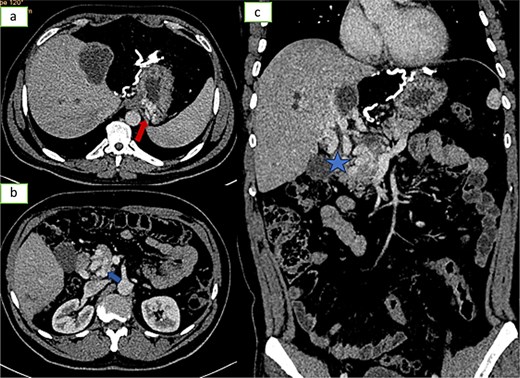

![Axial sections of an injected abdominopelvic CT scan [(a) arterial temp; (b) portal temp] and (c) coronal reconstruction showing portal hydatidosis with the presence of a cavernoma of the hepatic hilum.](https://oupdevcdn.silverchair-staging.com/oup/backfile/Content_public/Journal/jscr/2025/5/10.1093_jscr_rjaf337/1/m_rjaf337f3.jpeg?Expires=1778282696&Signature=WZSVNjAljj9A2J4gwzBvEgWhbngdokVsEzYzgcn~BzYJiNiaexv-lQQaVqBFL7fMppyToj0n16kgYA8ZpvQYQ8QR4WYeWoKagXCx~VcnLCsckuN4obar4k9ul5hZb3slXUxW9q0CeUc3VstGsGQZgauxcJ37cS~cY3y~wlZ6wyB0JlU~8ItzS7nBLU~mLtMCmYajNLIjgXeU9ANvCvPNzcmoHxoS3SNk0ALWODB-w6QP9h4~5h7ZyDE30vqVTxLmqrxdBQl6qrwWdxPmgCnQ1y8puu2kzml3L5e0BTM6xsNZUhyuWrvgX-yHsIabyIGzuEHOnX5-iU9hSEWjr4FRPQ__&Key-Pair-Id=APKAIYYTVHKX7JZB5EAA)

Axial sections of an injected abdominopelvic CT scan [(a) arterial temp; (b) portal temp] and (c) coronal reconstruction showing portal hydatidosis with the presence of a cavernoma of the hepatic hilum.